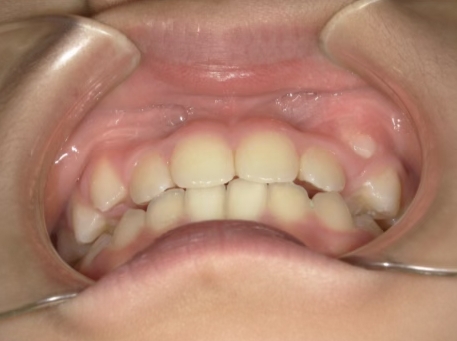

治療前① 小1:6y8m 初診

| カウンセリング・診断結果 | 前歯の生え変わり時期に来院されました。(写真①) 乳歯列期に受け口の既往があり切端咬合になりそうなため、受け口に対する矯正治療の考え方と対処法、当院のコンセプトを説明したところ治療を希望されたので診断を行いました。 診断の結果、上顎骨に対し下顎骨が長く、骨格的な構造も下顎突出型反対咬合(下顎骨が適切な位置よりも前に出ているタイプの受け口)と分かりました。 顔立ちは、中顔面が引っ込んだように見えるコンケーブに移行中です。 機能的な問題として低位舌があるため受け口の悪化が考えられることも説明し、以下の治療を提案しました。 |